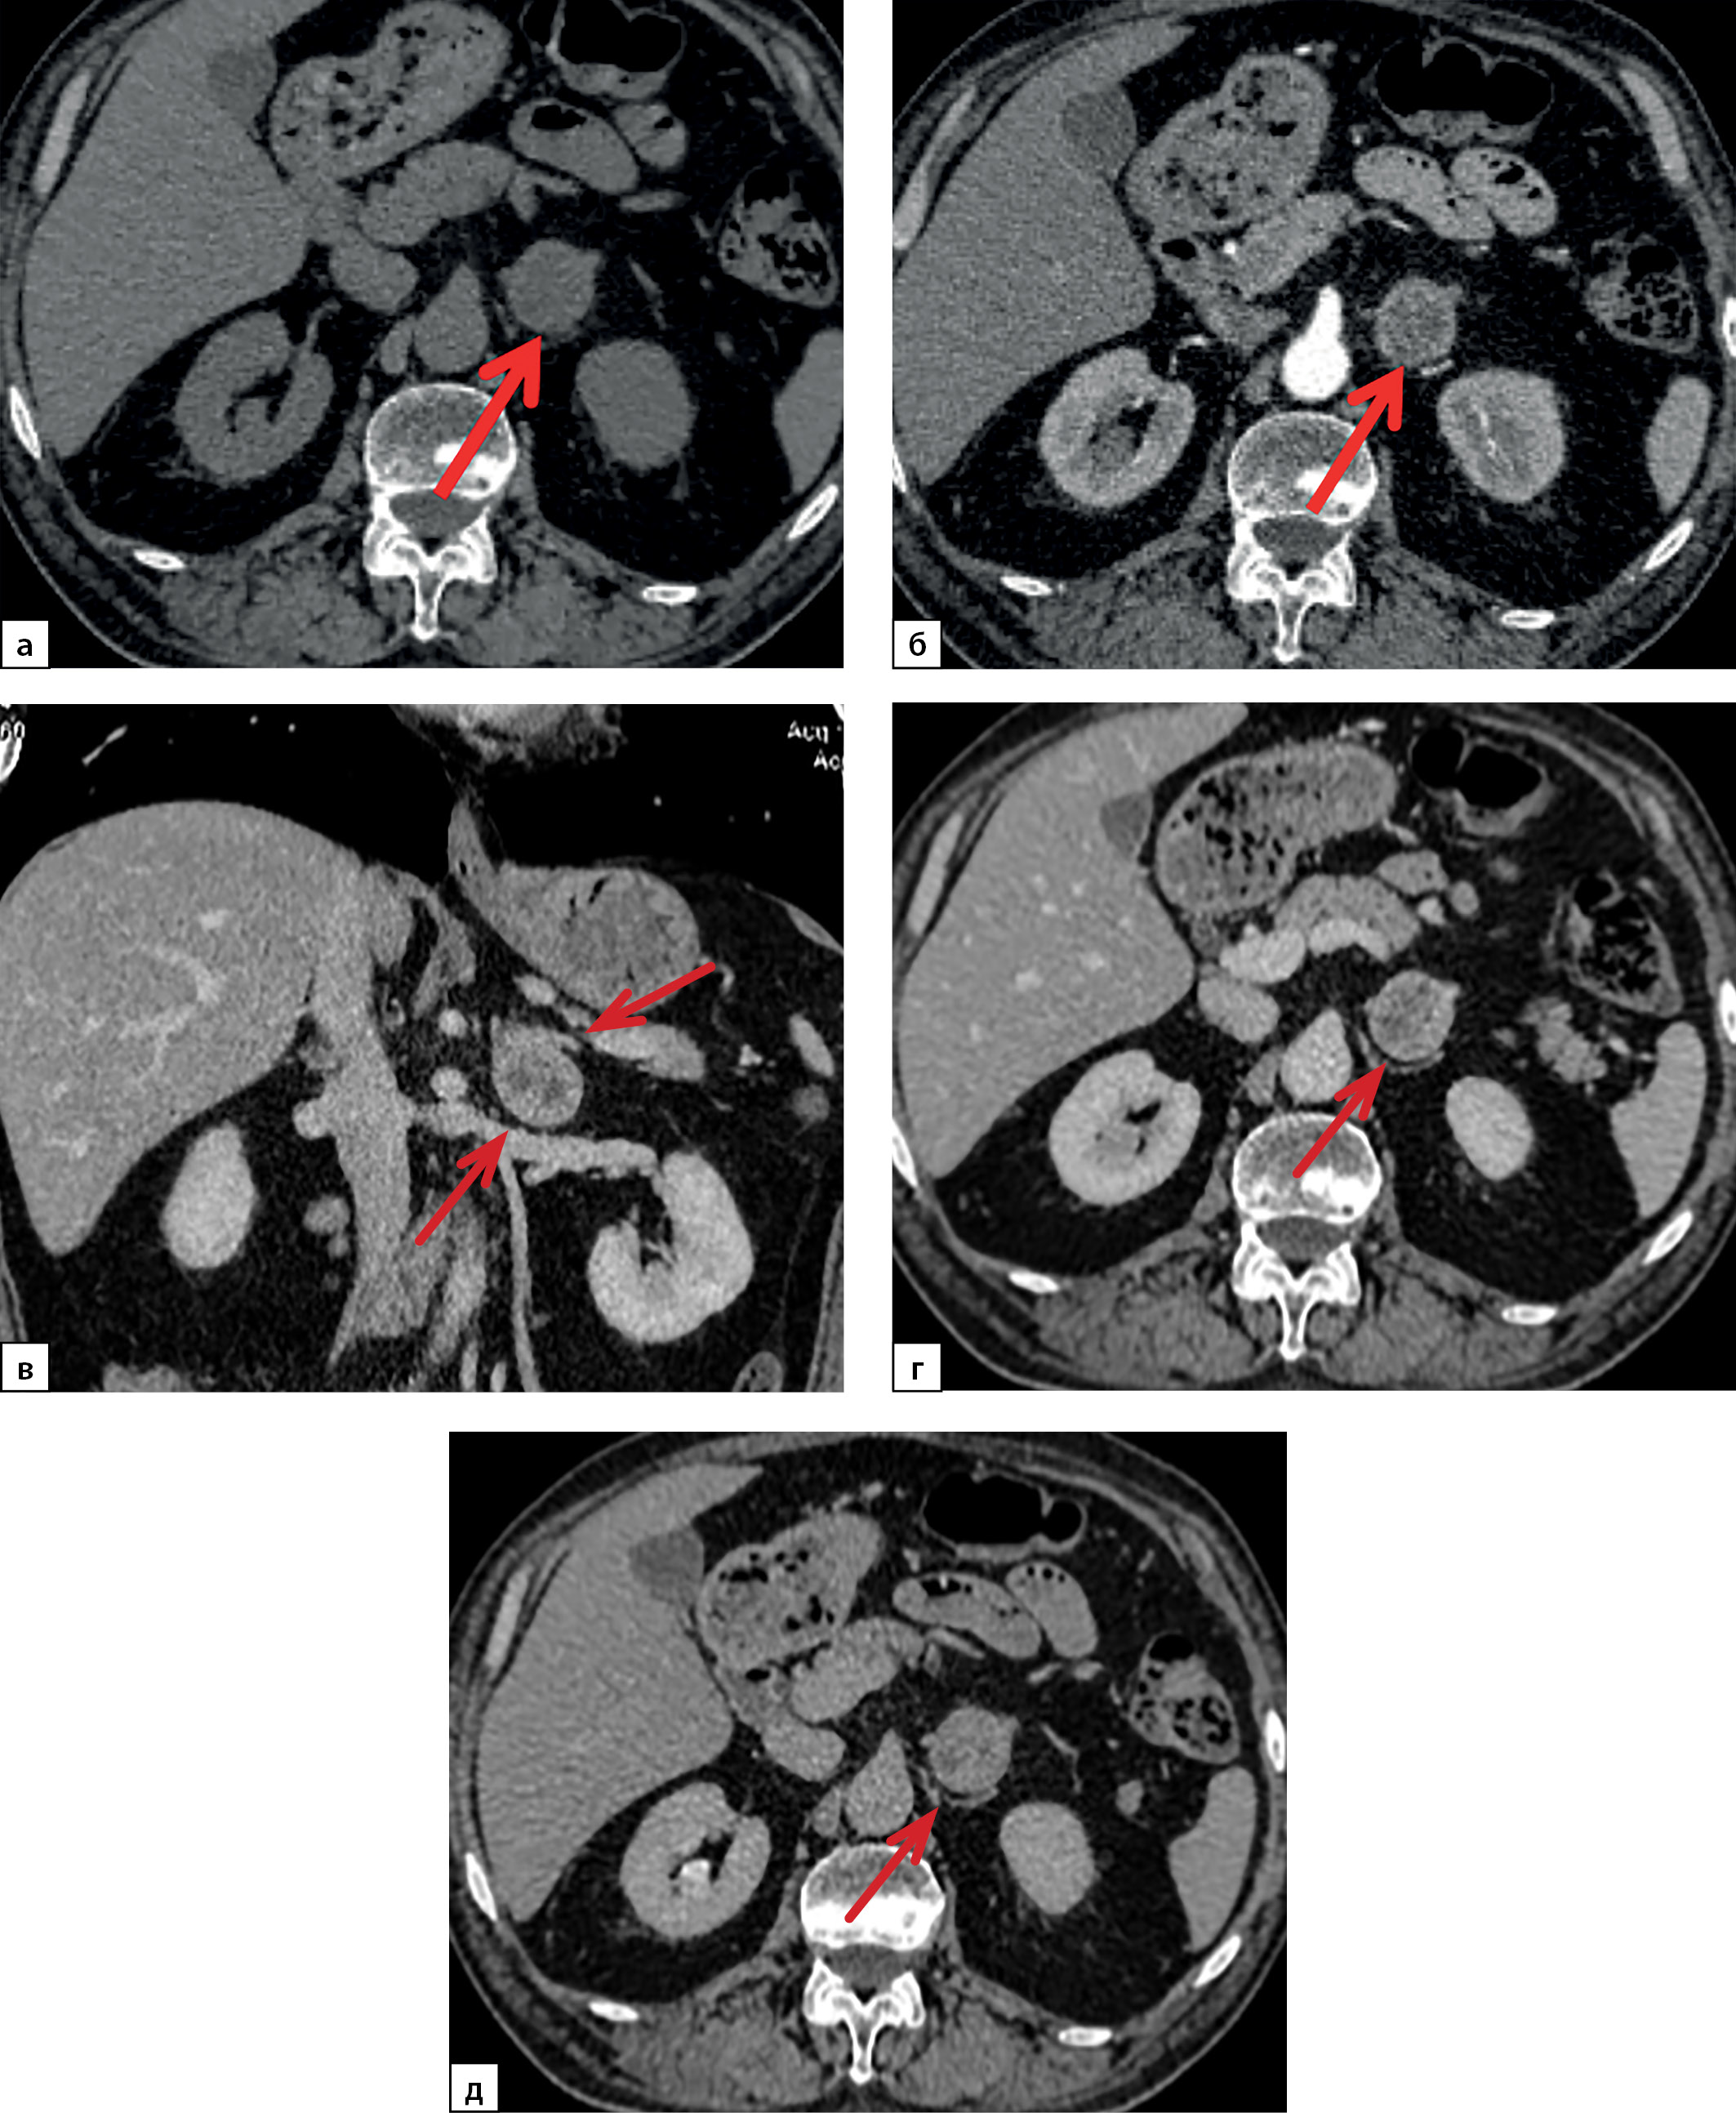

По результатам проведения МРТ ХСО с контрастированием турецкое седло расширено до 10,7×17,4×12,3 мм, анте- и параселлярно слева определен участок с изоинтенсивным магнитно-резонансным (МР) сигналом размерами 6,6,×6,7×10 мм с четкими ровными контурами, воронка гипофиза расположена справа от срединной линии, хиазма и кавернозные синусы интактны. На серии постконтрастных МР-томограмм отмечено неинтенсивное накопление контрастного вещества обнаруженным участком анте- и параселлярно слева (рис. 1).

Рисунок 1. Магнитно-резонансная томография

хиазмально-селлярной области с контрастированием:

а, г — Т2-ВИ,

б, д — Т1-ВИ,

в, е — Т1-ВИ с контрастированием.